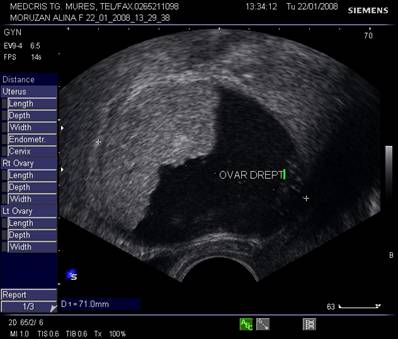

Fig. nr.391.

Endometriom ovarian vechi ,recidivat postoperator,

situat retrouterin

( sageata ). Se remarca ecogenitatea crescuta si asemanatoare ecostructurii endometriale uterine.